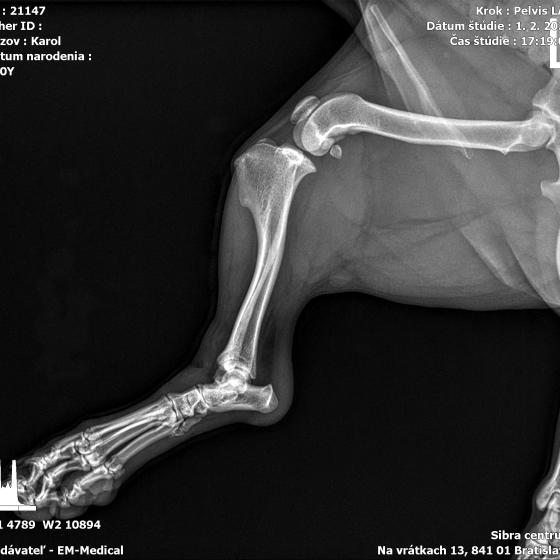

Karola nám doviezla pani, ktorá ho našla, asi jediná dobrá duša, ktorá pri ňom neprešla so zatvorenými očami. Ihneď sme s krpcom utekali na veterinu aby sa zistila závažnosť jeho zranení. Hneď pri prvých RTG snímkoch sa ukázala obojstranná fraktúra panvy, taktiež fraktúra krídla panvy a keby mu to chudákovi nestačilo, do tretice sa objavila zlomenina stavca. Karolko mal neznesiteľné bolesti, ale krásne prečkal vyšetrenie lebo vedel, že je v dobrých rukách a dostáva sa mu pomoci. Po nálezoch sme okamžite kontaktovali neurológiu a ortopédiu na veterinárnej klinike Sibra - centrum veterinárnej medicíny, kde sme dostali hneď termín na príjem.